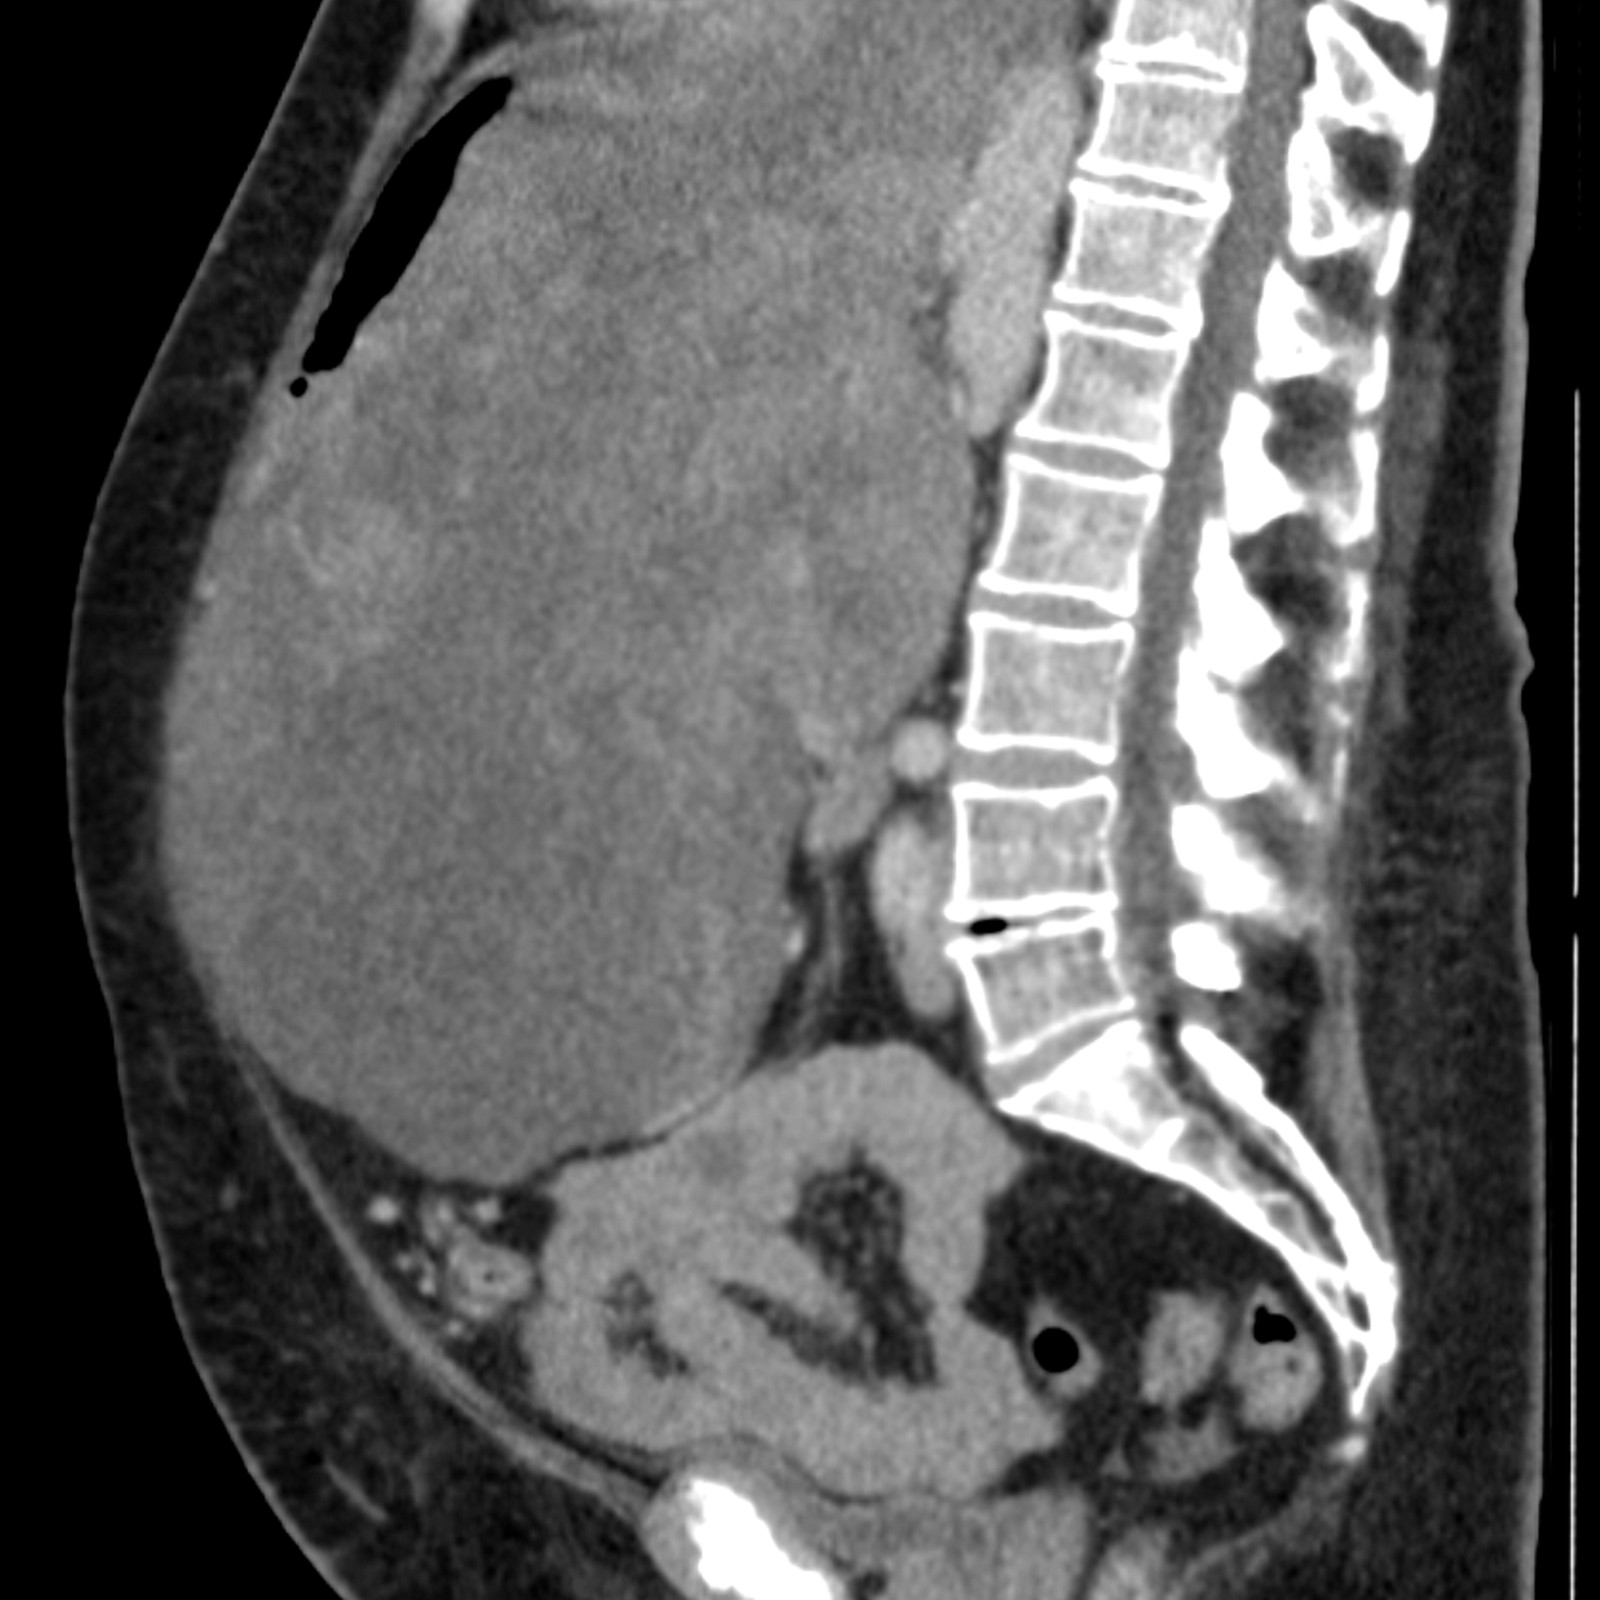

Nisan ayı başında Prof. Dr. Bektaş ve ekibi, 65 yaşındaki bir kadın hastadan tam 8,5 kilogram ağırlığında kötü huylu bir tümör çıkardı. Gesundheit Nord Klinikler Birliği'nin açıklamasına göre bu dev kitle, hastanın karaciğer, mide ve bağırsak sistemini karın duvarının kenarına kadar itmiş, hatta diyaframdaki bir boşluktan göğüs kafesine doğru yayılmıştı.

Birkaç ay öncesine kadar tümörün varlığından habersiz olan hasta, giderek kötüleşen sağlık durumu, yemek yiyememe ve üç ay içinde 22 kilo kaybı yaşayınca doktoru tarafından hastaneye sevk edildi. Bilgisayarlı tomografi görüntülerindeki devasa kitle karşısında doktorlar şaşkınlığa uğradı.